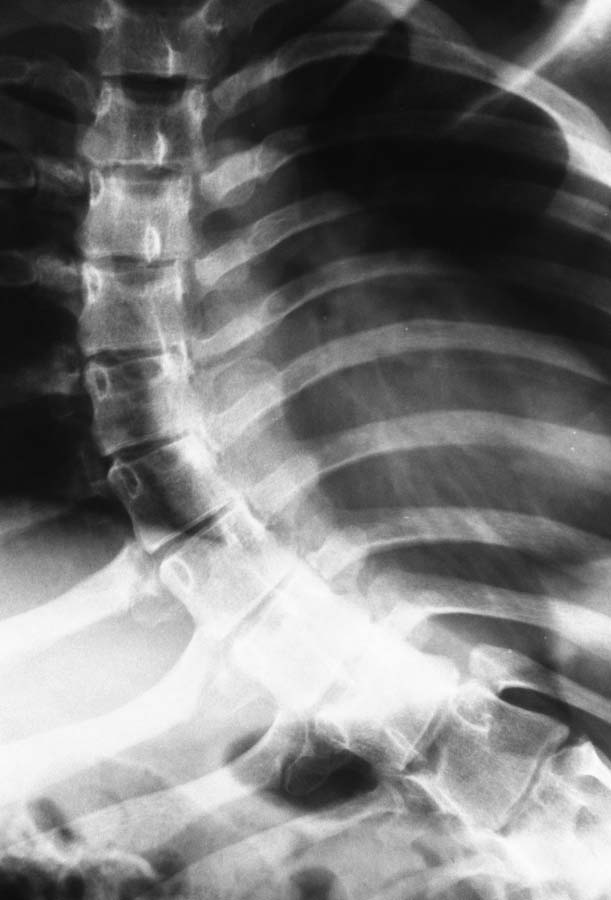

Пациентка 1992 г.р. Болеет ДЦП с рождения. до 2005 г. наблюдалась у неврологов , ходила с

поддержкой. В 2005 г. перелом средней трети бедра. Лечилась консервативно в больнице

Краснодара.

После лечения постепенно стала наростать укорочение конечности и искривление

позвоночника. На представленных Р-гр состояние на сегодняшний день. больная занимает

вынужденное полулежачее состояние. Вопрос где нибудь на просторах РФ могут помочь?????